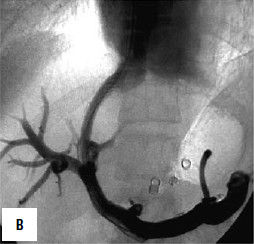

Рис. 90. Операция чрезъяремного внутрипеченочного портосистемного шунтирования (TIPS): А – схема операции; Б – этап постановки стента; В – контроль проходимости стента